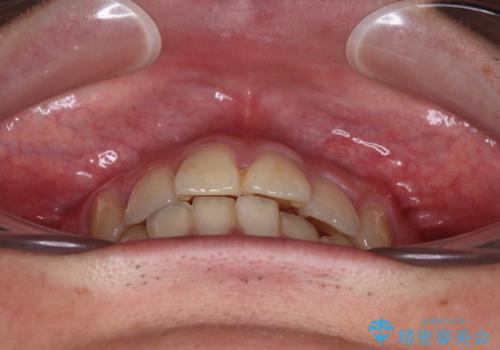

- 高校生の時に行った抜歯矯正の後戻りを気にして来院された患者様です。

インビザラインでの治療を希望されていて、デコボコの程度が中等度であり、安価なパッケージにて対応可能と判断されたため、インビザライン・モデレートを用いて矯正治療を行うこととしました。